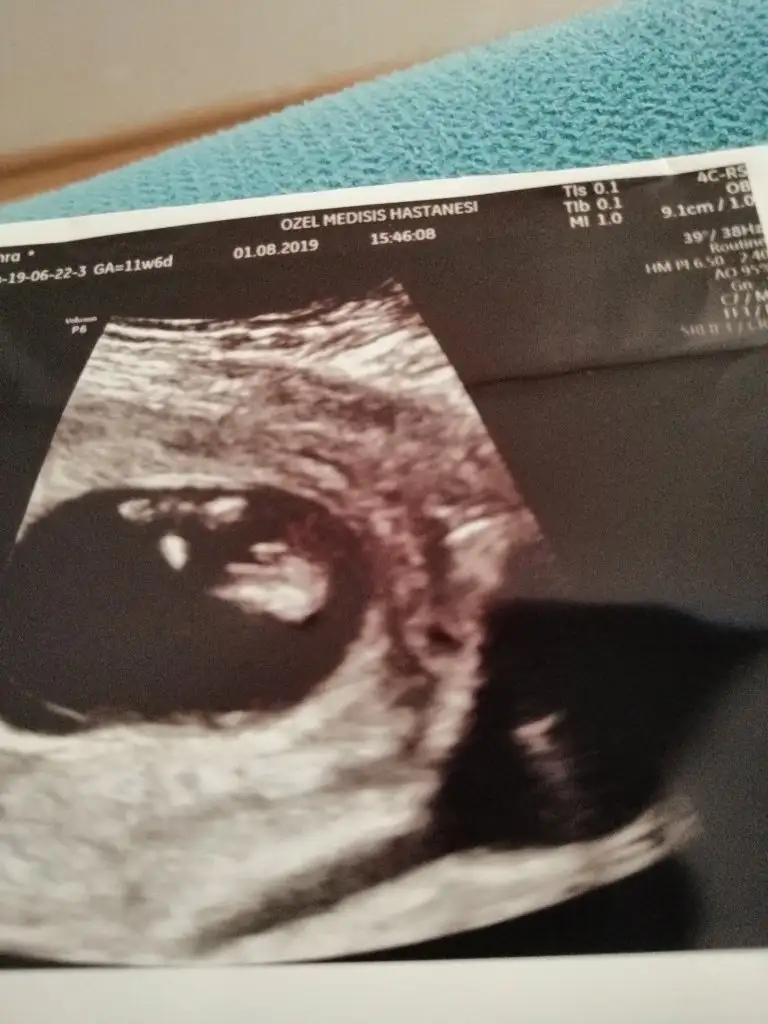

Kızlaar benim bebişede bi yorum yapsanız bende merak ediyorum cinsiyeti

Eki Görüntüle 2294674

Eki Görüntüle 2294675

Eki Görüntüle 2294676